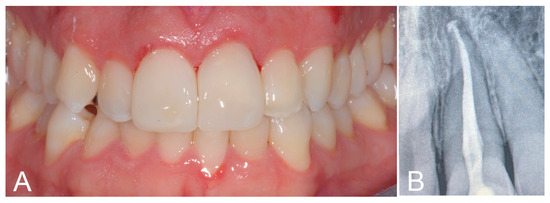

2. Case Report